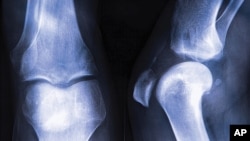

Osteoporosis in leg join

กระดูกของมนุษย์ทุกคนไม่ว่าหญิงหรือชาย จะอ่อนแอเมื่อแก่ตัวลง และมีโอกาสที่จะเกิดอาการที่เรียกว่า Osteoporosis หรือ "โรคกระดูกพรุน" ซึ่งหมายความตามชื่อ ก็คือผู้ป่วยด้วยโรคนี้จะมีรูเล็กๆ ตามกระดูก ทำให้กระดูกอ่อนแอหรือบางลง และแตกหักง่าย เช่น เมื่อถูกกระแทกหรือหกล้ม ซึ่งบางครั้งอาจอันตรายถึงแก่ชีวิต โดยเฉพาะบริเวณกระดูกสะโพก